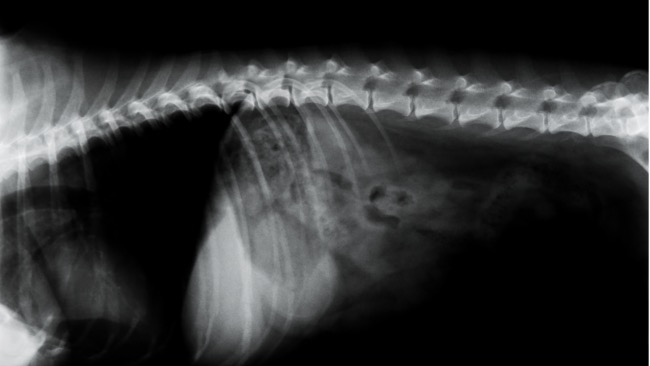

Cześć, nazywam się Milena a to mój piesiek Brokat. Brokat ma 4 lata, niestety przeszedł już 3 operację kręgosłupa w swoim życiu. Leczenie, specjalna karma, operację, rehabilitacja pochłaniają ogromne kwoty co spowodowało zaciągnięcie przeze mnie kredytów na kwotę 65 tys złotych. Brokat ciągle potrzebuje rehabilitacji. 2 razy w tygodniu jeździmy na prądy oraz na bieżnię wodną, a każda wizyta kosztuje mnie 200 zł. Brokat ma problemy z chodzeniem, nie może skakać ani wchodzić po schodach. Boję się ze nie finansowo nie podołam jeśli będzie potrzebna kolejna operacja. Bardzo proszę o najmniejszą kwotę która pomoże poprawić mu standard życia. Dziękuję Milena Jaworek.